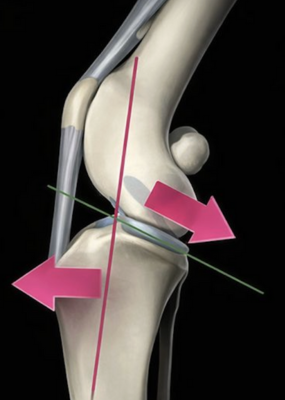

Le chien présente une pente tibiale entrainant lors de rupture de ligament croisé une poussée tibiale craniale et un glissement du fémur caudalement.

Concrètement, le chirurgien réalise une ostéotomie circulaire du tibia proximal, puis fait pivoter le plateau tibial afin de réduire son angle. Cette modification neutralise la « poussée tibiale craniale » qui, lors de l’appui, provoquait le glissement anormal du tibia sous le fémur. L’os est ensuite stabilisé à l’aide d’une plaque spécifique et de vis, généralement laissées en place à vie si elles ne provoquent aucune gêne.

On peut comparer cette intervention à un rééquilibrage de pente : là où une surface inclinée favorisait le glissement, la TPLO la rend plane et stable.